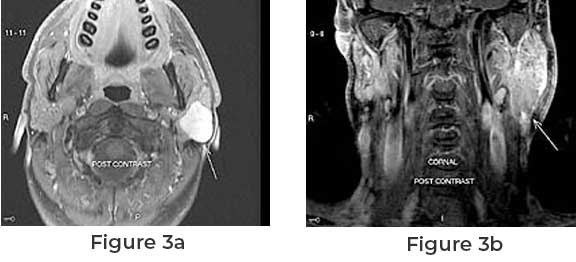

There is generally little discomfort associated with parotid tumors, which produce swelling in the cheek or jaw. Others include numbness, scorching or prickling sensations in the face, or a lack of facial mobility. A young kid may be distressed by the stigma of a visible facial scar following parotid surgery. The surgical method of parotidectomyand facelift incision is discussed further to understand them. In a modified facelift incision, thirty patients with a benign parotid gland lesion received a partial superficial parotid tumor surgery upon completion of the procedure, all patients had outstanding cosmetic results and full facial nerve function. For (partial) superficial parotid tumor surgery, the parotid gland might be exposed through the facelift incision. As an option, it can be provided to individuals who have a tiny, movable tumor in the tail of the parotid gland and a clear explanation for their condition. Mucoepidermoid cancer is a unique kind of tumor.

The facelift incision is the best way of endowing with adequate exposure of the parotid gland for superficial parotidectomy. It can be offered as an alternative to a select group of patients, who present with a small, mobile tumor in the tail of the parotid gland and an explicit request for an invisible postoperative scar.